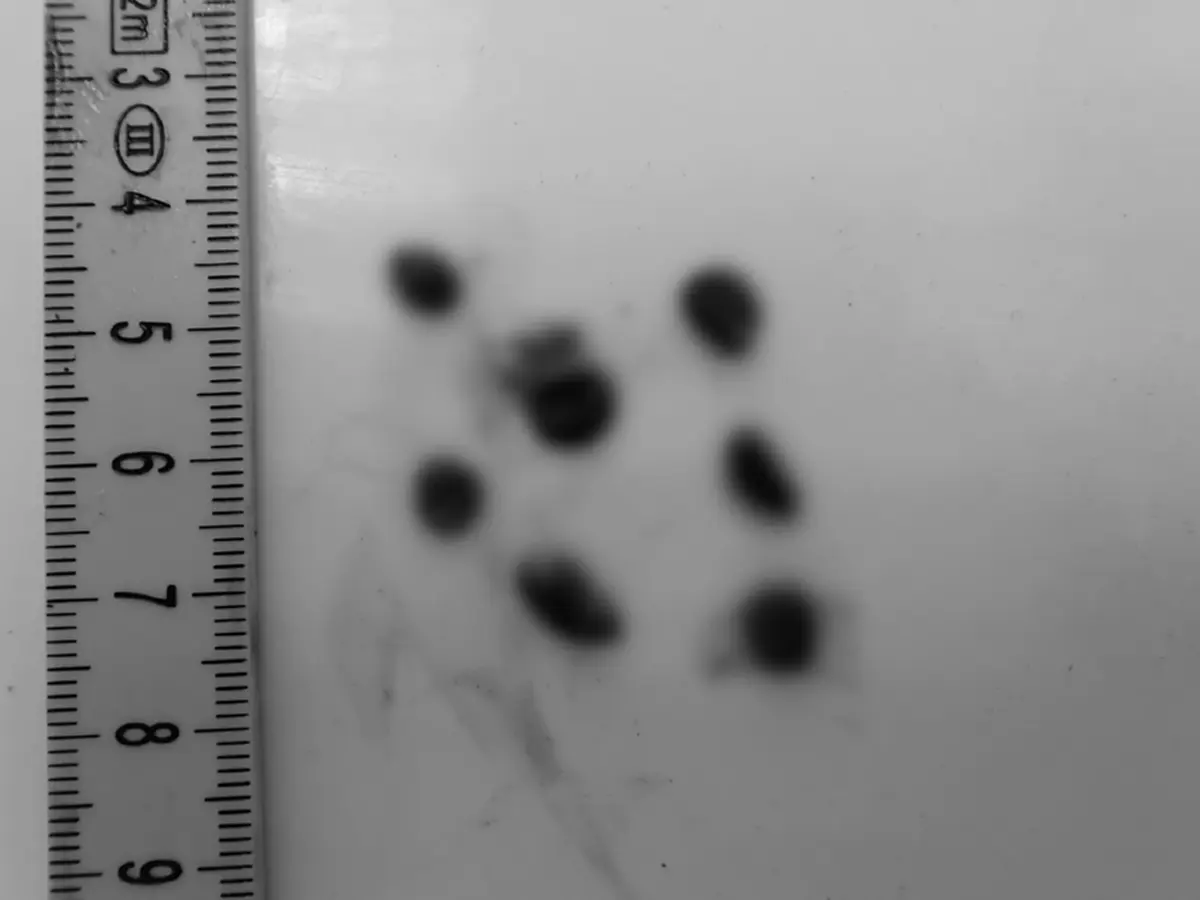

ผลการชันสูตรเบื้องต้นพบชั้นไขมันบาง (1.2–1.8 ซม.) และกล้ามเนื้อฝ่อเล็กน้อย บ่งชี้ถึงภาวะพร่องโภชนาการระบบทางเดินหายใจพบพยาธิใบไม้ในรูจมูกเล็กน้อย และเศษกรวดในหลอดลมกระเพาะอาหารว่างเปล่า มีเพียงของเหลวปนเศษหญ้าเล็กน้อย และพบพยาธิตัวกลมในกระเพาะและลำไส้เล็กจำนวนมาก (98 ตัว) ลำไส้ใหญ่มีอุจจาระอัดแน่นและค่อนข้างแห้ง